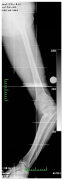

ORTHO-SUV FRAME – is a new generation computer assisted external fixation device. Ortho-SUV Frame is an advanced extension of traditional Ring Fixator developed in Russia as a single step solution for treating complex deformities and fractures. It reduces the time for deformity correction. The main advantage of SUV is the perfection of correction in deformity correction. It corrects the deformity in all plane.

With traditional method of ilizarov deformity correction, it is a time consuming procedure and patient needs to attend the doctor so many times. Here the patient himself can correct the deformity by rotating the struts on the SUV .once the deformity corrected then the SUV can be removed and normal hinge joint can be connected./p>